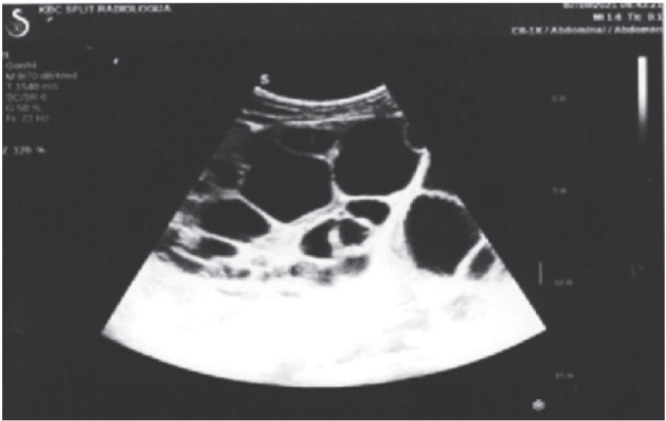

This case report presents a 43-year-old worker (welder in the locksmith trade) from Bosnia and Herzegovina who was diagnosed with advanced hydatidosis during a preventive medical examination. The patient had a history of frequent close contact with dogs at home and at work and reported a long-standing sensation of heaviness in the left side of his abdomen. As part of his routine occupational health examination, he had a complete laboratory testing, abdominal ultrasound, multislice computed tomography (MSCT), and a consultation with an infectious disease specialist and abdominal surgeon. Imaging revealed multiple cystic formations in the left hemiabdomen and a cyst in segment VIII of the liver, confirming the diagnosis of multivisceral echinococcosis. The patient was promptly treated with preoperative (and postoperative) albendazole to reduce the cyst size and prevent complications. This case highlights the critical role of ultrasound in the diagnosis of hydatidosis, especially in an occupational medicine context. As part of preventive screening, ultrasound is a valuable tool for the early detection of echinococcosis in workers in high-risk environments. Early diagnosis allows for timely intervention, reducing the risk of disease progression to an advanced stage. This case underscores the importance of implementing effective epidemiological strategies, including regular screenings and awareness campaigns, in order to control the spread of echinococcosis in endemic regions.

本病例报告涉及一名来自波斯尼亚和黑塞哥维那的43岁工人(锁匠行业的焊工),他在预防性医学检查中被诊断患有晚期包虫病。患者有在家和工作中经常与狗密切接触的病史,并报告其左腹部长期有沉重感。作为常规职业健康检查的一部分,他做了完整的实验室检查、腹部超声、多层计算机断层扫描(MSCT),并咨询了传染病专家和腹部外科医生。影像学显示左半腹多发囊性形成,肝脏第八节段一囊肿,确认多脏器包虫病的诊断。患者术前(术后)及时使用阿苯达唑治疗,以减小囊肿大小并预防并发症。本病例强调超声在包虫病诊断中的关键作用,特别是在职业医学背景下。作为预防性筛查的一部分,超声是在高危环境中早期发现棘球蚴病的宝贵工具。早期诊断可以及时干预,减少疾病进展到晚期的风险。这一病例强调了实施有效的流行病学战略的重要性,包括定期筛查和提高认识运动,以控制棘球蚴病在流行地区的传播。